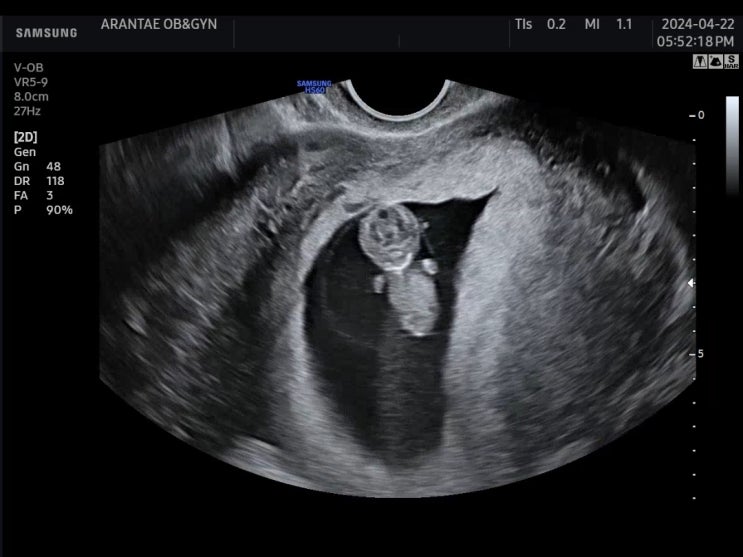

계류유산 후 임신이 되었다. 임밍아웃은 최대한 늦게, 25주까지의 기록

이 포스팅을 언제 써야 하나 고민이 많았는데, 이제는 정말 안정기에 들어온 것 같다는 생각이 들어 기록을...